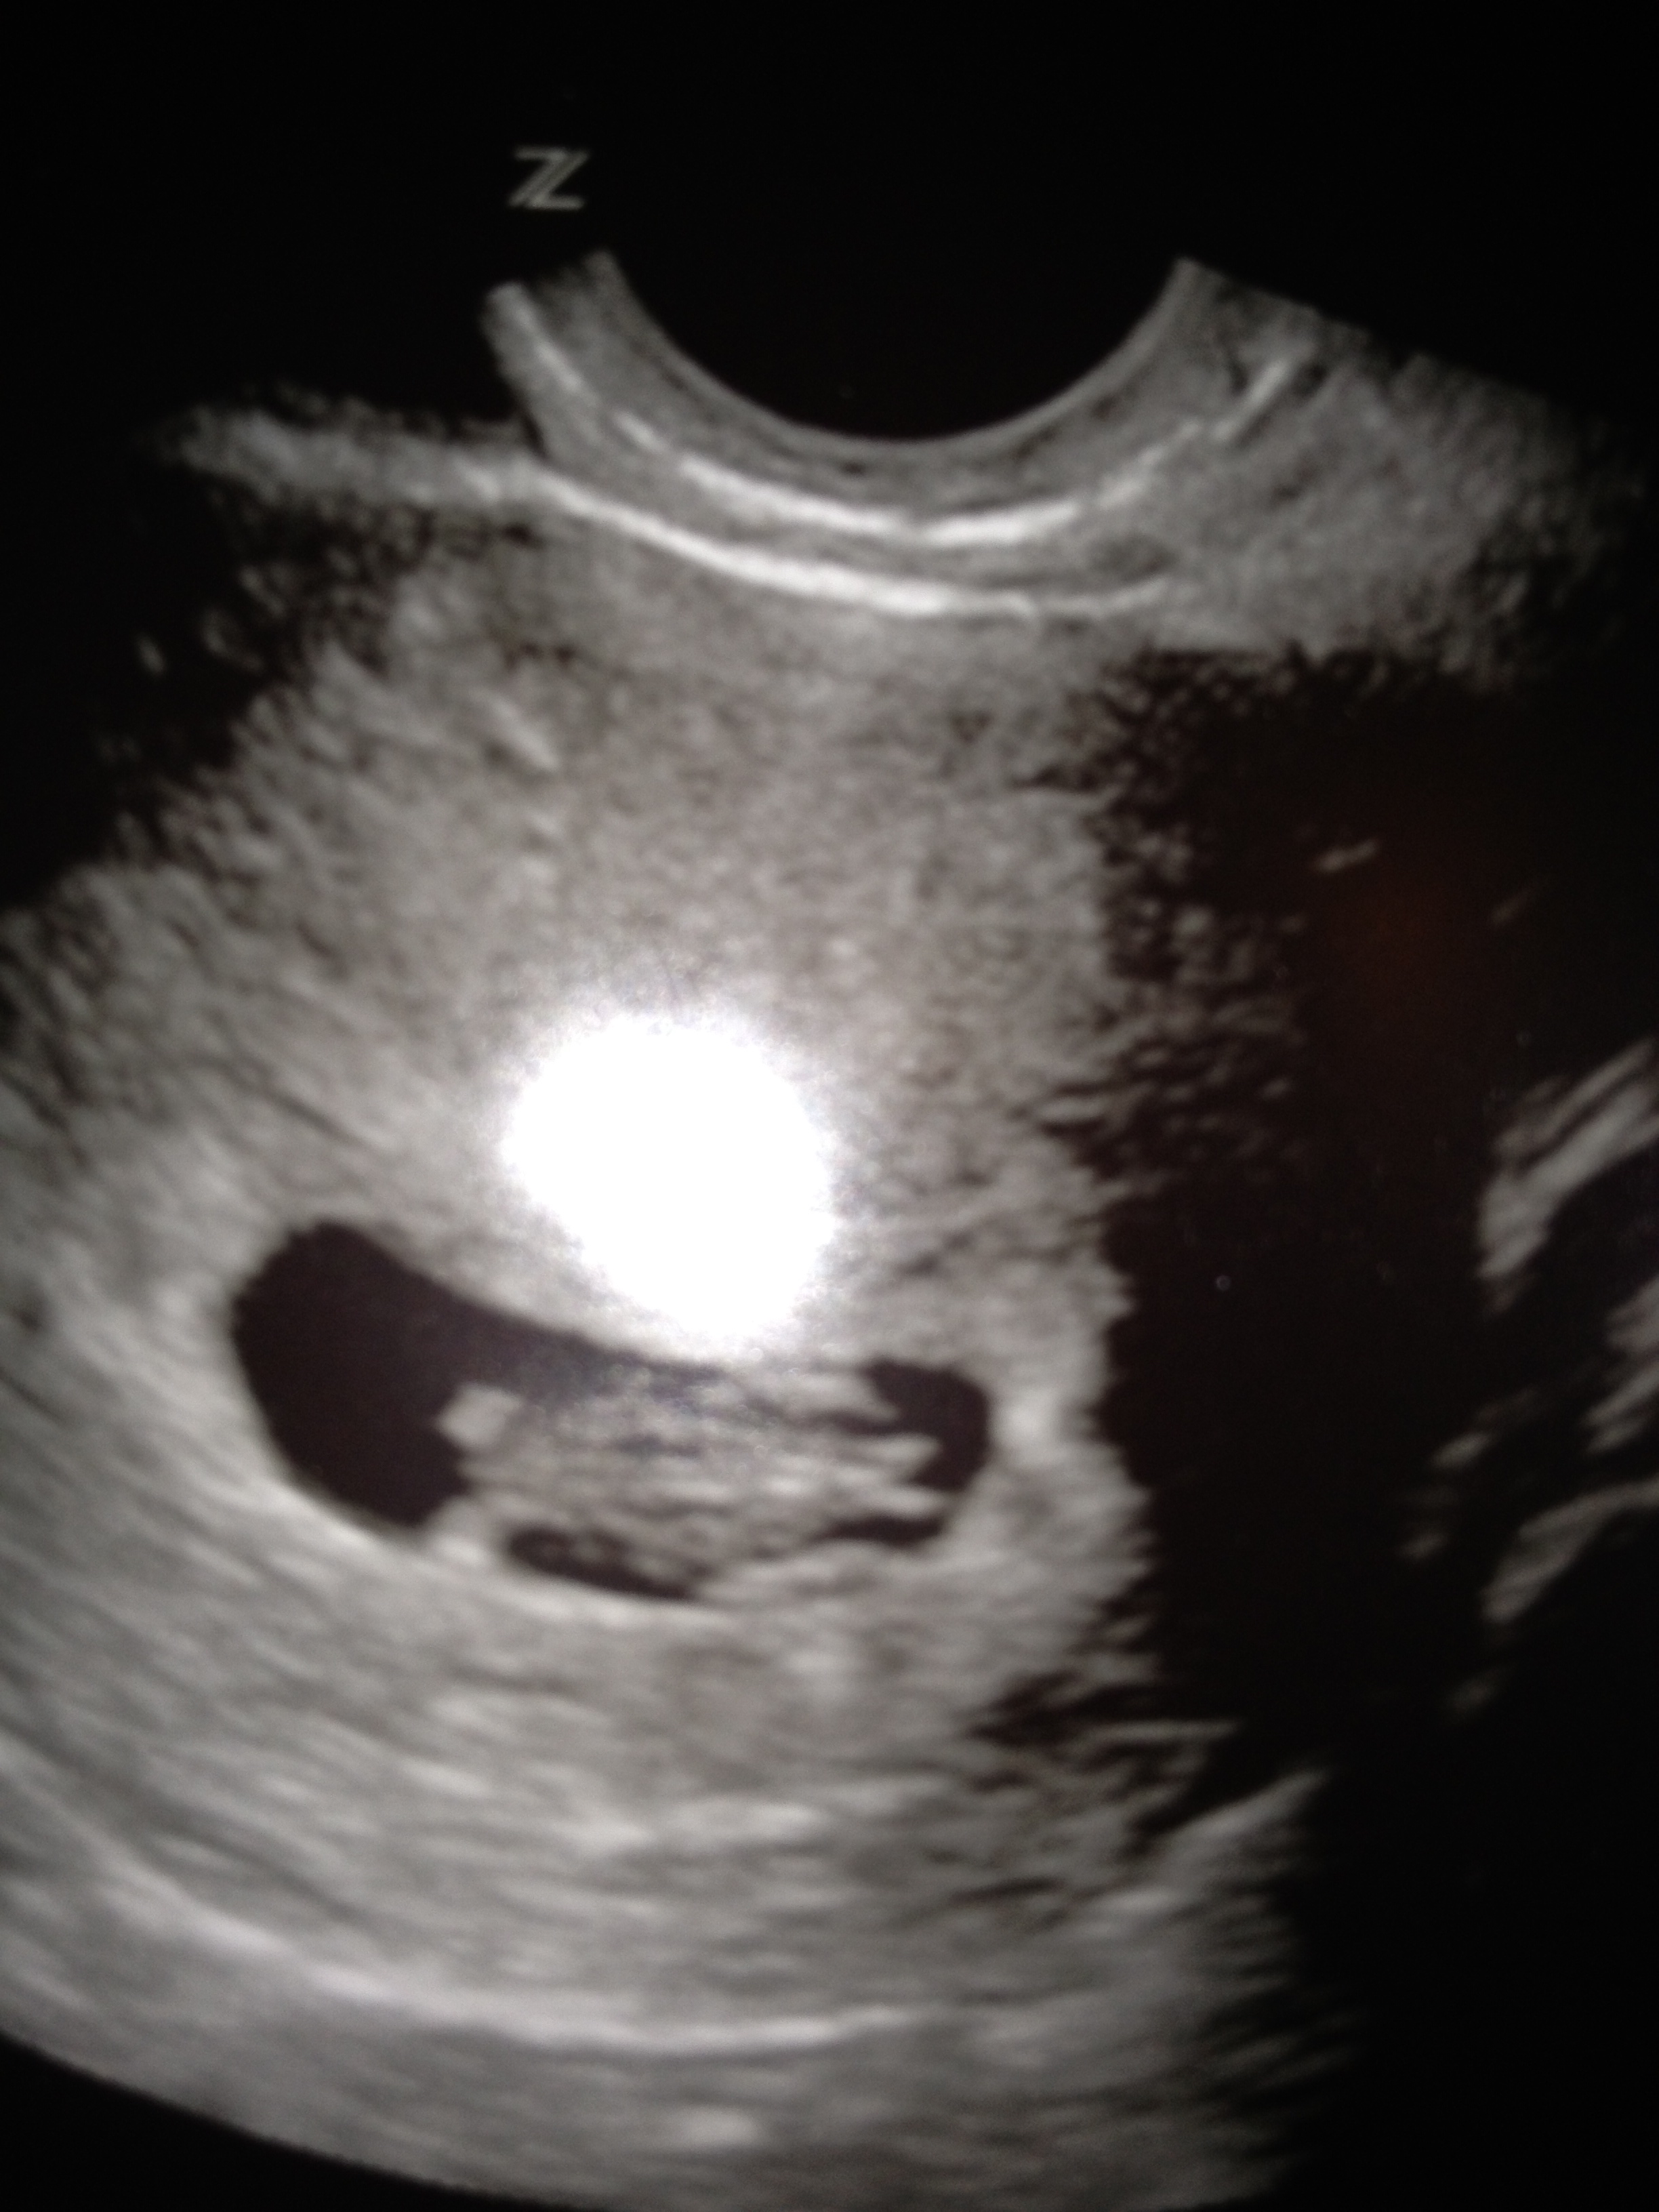

The doctor introduced herself, congratulated us, and then went into a brief explanation of what we could expect in the months to come. At this point, I’m still pretty “floaty,” but a little more excited. I left the room briefly while the doctor conducted some of the girly tests; discretion is the better part of………well sometimes it’s just better. When I was summoned back into the room, the ultrasound was already in place and it took me a second to realize what I was looking at on the screen. Right there was Ninja Baby! Mind you, it was just 2cm, but there it was. As the doctor adjusted the ultrasound, we could even see its heart beating, kind of like ET’s, except without the glowing finger and Reese’s Pieces. And then, as if to say “What’s up,” Ninja Baby kicked its little nubby leg four times! Even at this age, my baby understands the importance of a good leg kick. With another flick of a button, we then heard the baby’s heart. A solid 120 beats per minute. Slow for a metal song but perfect for a developing baby!

As the doctor wrapped up the appointment, she printed out a strip of pictures from the ultrasound. Definitely better than some Spiderman stickers! I’m not sure I’ve smiled that much for some time. Then again, I’m not sure the people in the elevator really wanted to see the pictures, but that’s ok. “Floaty” is gone. Seeing that ultrasound hit me like a ton of bricks; little, fluffy, baby-safe bricks. We have quite a road ahead of us, and this little guy or gal is real. Ninja Baby is here to stay.